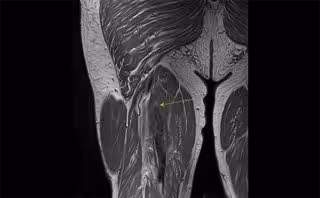

Archivo - Los músculos de cuatro pacientes con Covid crítico de un total de 18 personas crecieron en lugar de encogerse. - UNIDAD DE RADIOLOGÍA DE CREUBLANCA - Archivo

Al respecto, el doctor Mostien y sus compañeros del Hospital Jessa (en Hasselt-Bélgica) y la Universidad de Hasselt tomaron biopsias musculares de pacientes con Covid en estado crítico antes y después de la admisión a cuidados intensivos. Un total de 18 pacientes fueron analizados para el proyecto. Concretamente su vasto lateral, el músculo más grande y poderoso del muslo, biopsiado varias veces desde 1-3 días antes de la admisión en la UCI hasta 5-8 días después de la admisión. Los pacientes tenían una edad media de 69 años y el 82 por ciento eran hombres.